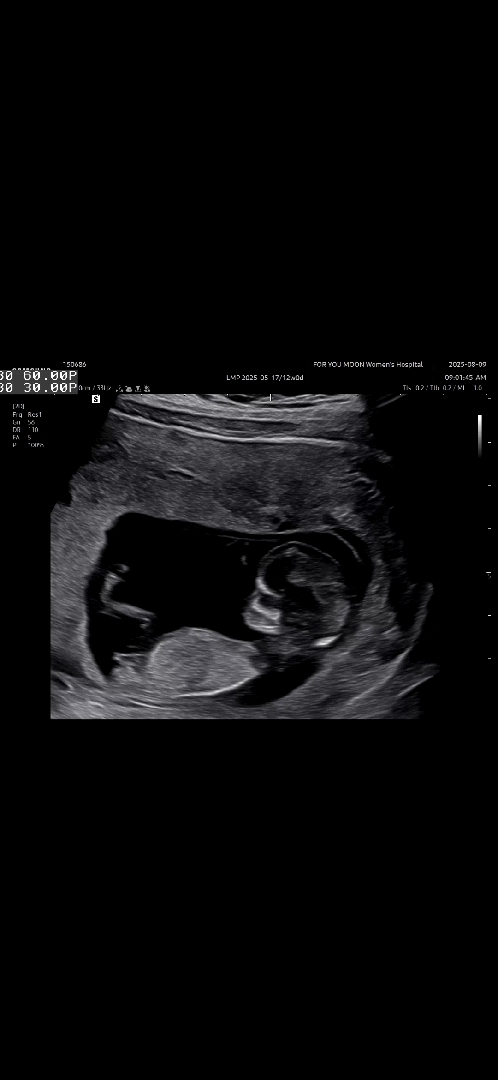

각도법고수님들 봐쥬세요!!

12주 0일인데 니프티하고는 왔는데 결과나오기 전까지 너무 궁금해요!!